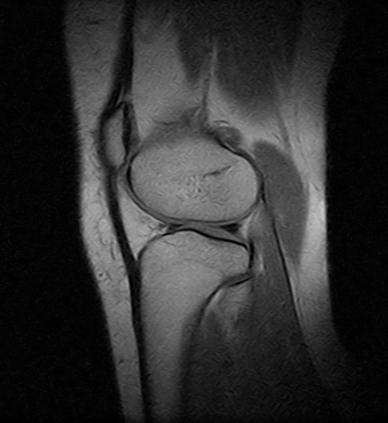

Ressonâncias Magnéticas Joelho

Se você pesquisa ressonâncias magnéticas joelho com eficiência e profissionalismo, não deixe de vir conhecer os serviços oferecidos pela RM Brasil.